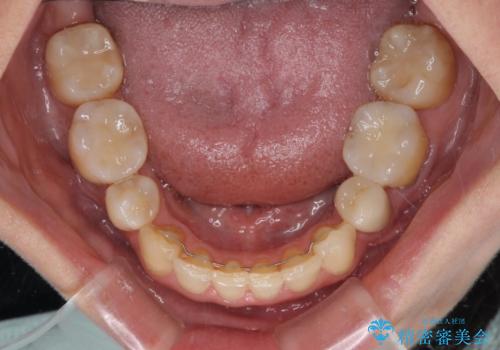

インビザライン・ライトは、製作できるアライナーの枚数に制限があるため、移動可能な量に限りがあります。

軽微な後戻りの治療であったため、十分に治療を行うことができました。

口を開けたときに金属が見えなくなり、患者様には大変満足していただきました。